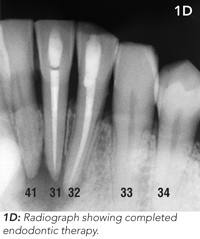

The patient underwent endodontic (root canal) therapy to the lower incisor teeth (31 and 32) and reported that the discharge ceased a week later. Photographs taken at 3-month follow-up showed resolution of the tract (Figure 1C and 1D).